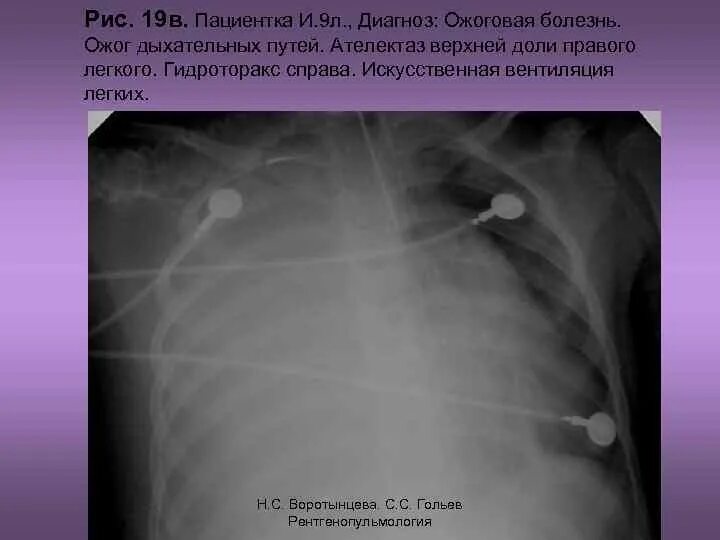

Ожог верхних дыхательных путей соответствует